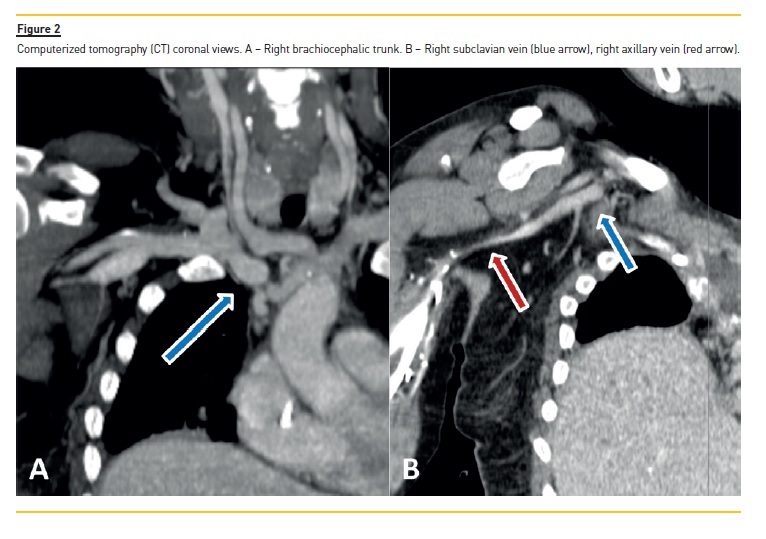

Although a whole‑body computerized tomography (CT) angiography revealed patent right subclavian and axillary veins (Fig. 2), it was not possible to place a catheter in this location after several attempts and therefore left femoral vein was considered as last vascular access site option. Although the implantation of a new catheter at this vein could theoretically jeopardize future kidney transplantation, taking into account the patient´s desperate clinical situation, a left femoral catheter was implanted. Peritoneal dialysis catheter implantation was also attempted without success due to multiple abdominopelvic adhesions. Considering the importance of maintaining femoral vascular patency to allow future renal transplantation, a multidisciplinary meeting involving the Nephrology and Vascular Surgery departments decided to use a Hemodialysis Reliable Outflow (HeRO) Graft. Blood cultures obtained before the procedure were negative.

The device was implanted by a surgical team from the Vascular Surgery Department (Fig. 3). Under general anaesthesia, central venous access was obtained in the right subclavian vein by standard Seldinger technique.